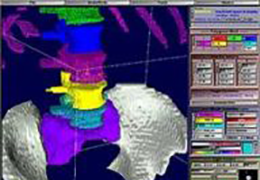

High-quality and fast 3D reconstruction and 3D rendering

Performs 3D reconstruction and volume rendering.

Instant and interactive surface extraction and export to STL and PLY formats.